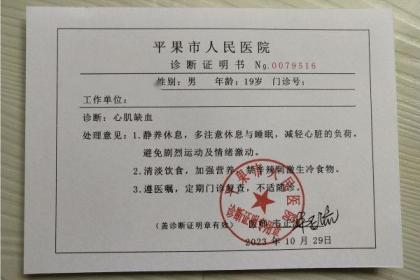

武汉惠鑫健康管理有限公司专业代开上海医院病历证明17267193882,诊断证明,医院病假条、病假单、请假条、病例单,医院休学证明、免军训证明、免体测证明,化验单、CT报告单、B超单、病理报告、心电图,三甲医院病例诊断证明、医院住院证明、医院出院证明,医院怀孕证明、结扎上环证明、流产引产证明,医院病危通知书、医院全套病历等等。长期与市区各大三甲医院保持良好关系,欢迎随时联系我们!

医院病假单主要就是由医生开取的一个关于身体的病状情况,在严重的情况下要请假休息才行。很多人在请假的时候不知道怎么开医院病假条,请直接联系我!只有写好医院请假条才能使自己在家里安心养病,休假也是为了自己的身体健康尽快恢复。医院一般不可以直接开病假条,但是经正规医院的医师检查后,可以为病人开具疾病诊断书、健康证明书等材料,而劳动者可以携带该材料去申请用人单位开病假条。

总之,现在很多情况都会要求开具各种各样的医院病历证明,譬如公司请病假,怀孕休假,学校办休学,免军训,免体免测等等。什么情况才能开具诊断证明?复杂也好,难办也好,放轻松一点,我们愿意为您代劳!